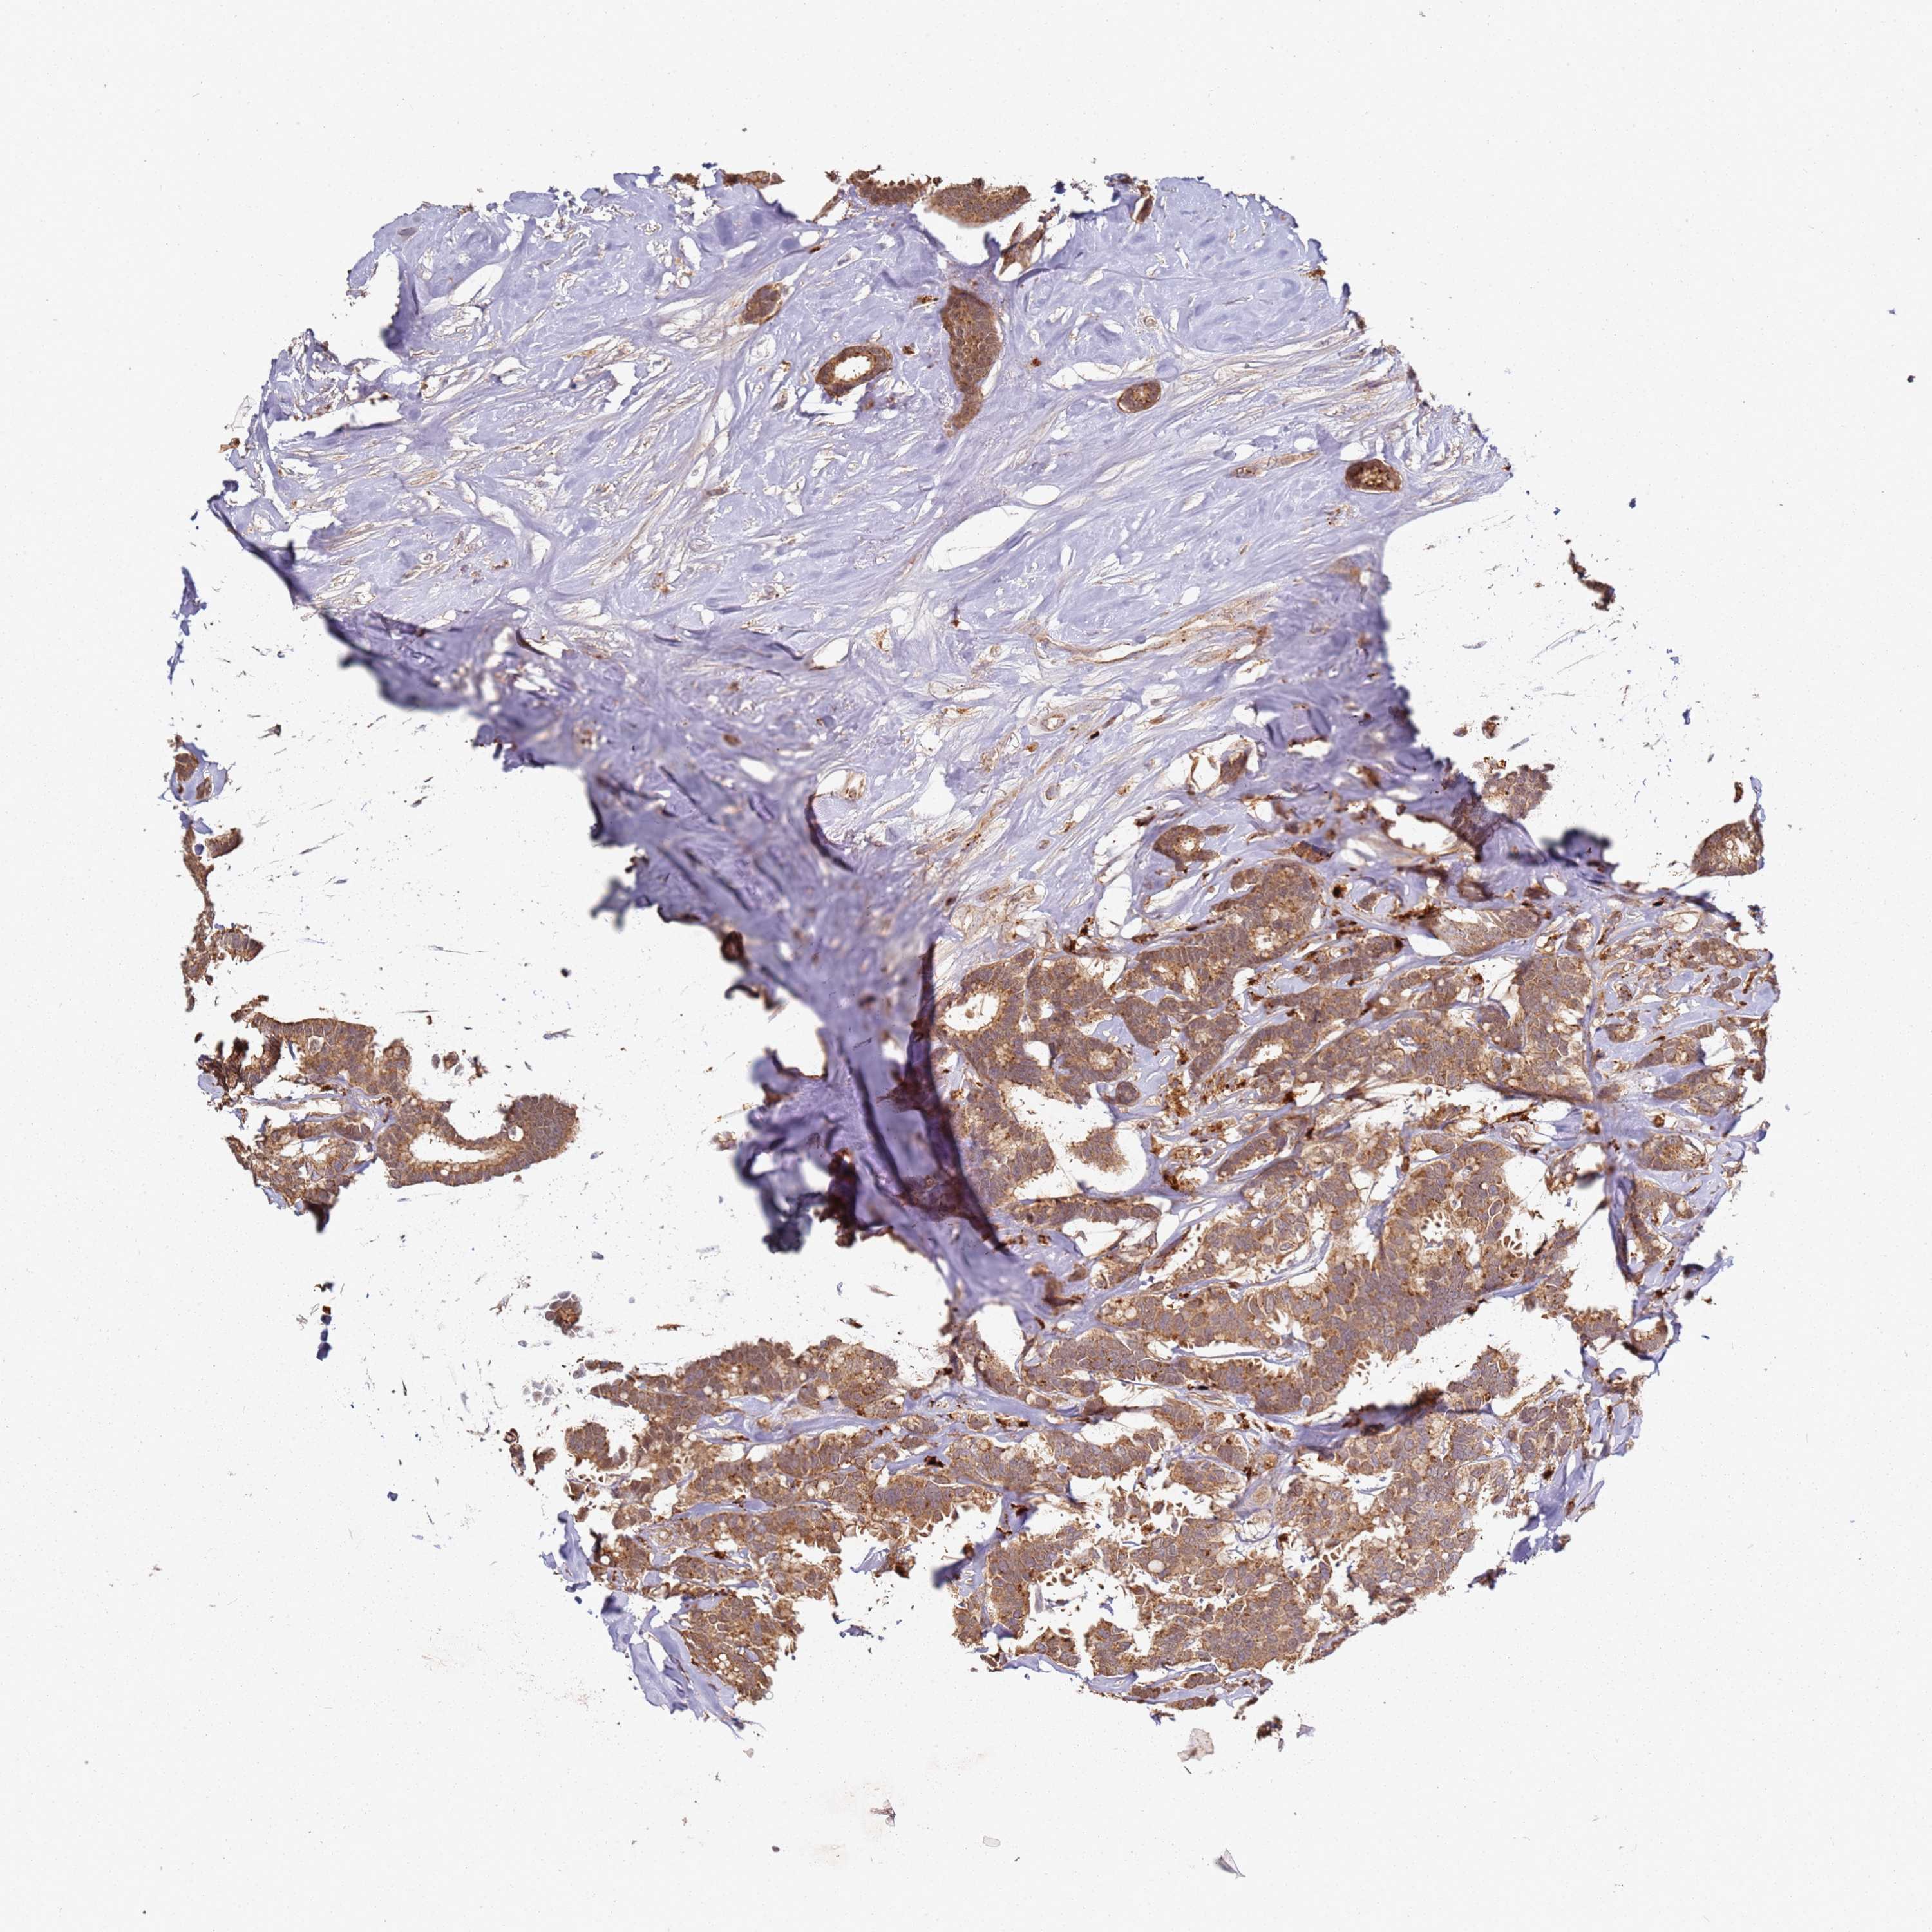

CANCER BREAST CANCER Show tissue menu

BRCA TCGA BRCA VALIDATION PROTEIN EXPRESSION

Breast cancer

Human cancer

Breast invasive carcinoma

SCGB2B2 is not prognostic in Breast Invasive Carcinoma (TCGA)